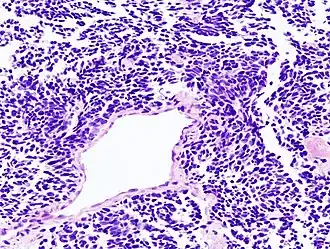

Carcinoom is een maligne of kwaadaardige vermenigvuldiging (woekering) van epitheelcellen. Epitheel is de bovenste laag cellen van huid of slijmvliezen. Net als andere maligne tumoren (kankergezwellen) worden carcinomen veroorzaakt door ongecontroleerde, lichaamsvijandige celdeling en manifesteren zich door infiltratieve groei (doordringen van het gezwel in omliggend weefsel), vorming van bloedvaten in het gezwel, de aanwezigheid van mitosefiguren in een histologisch preparaat en soms ook resten van dode cellen.